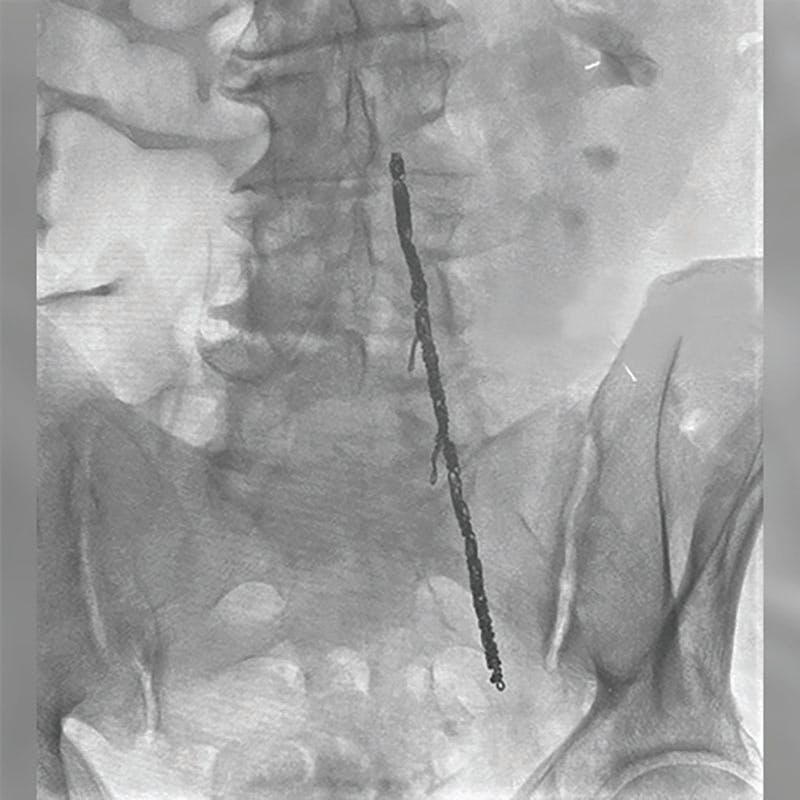

INTERVENTION

After informed consent, we elected to obtain a venogram with intravascular ultrasound (IVUS) and pullback pressures, as the CT scan workup showed a nutcracker phenomenon. Standard access of the right femoral vein was performed under ultrasound guidance. The left renal vein was cannulated and IVUS was used along with pullback pressures, which did not suggest that there was significant compression of the renal vein by the superior mesenteric artery. A venogram was obtained and showed significant reflux in the ovarian vein via collaterals (Figure 1).

Figure 1. Pre-embolization venography demonstrating recurrent reflux in the left ovarian vein with collateral filling following prior low pelvic coil placement.

The ovarian vein was cannulated and packed with Ruby Coils (Penumbra, Inc.). We utilized several 14-mm X 60-cm Packing Coils (Penumbra, Inc.) as well as a 12-mm POD® (Penumbra, Inc.) to secure the coils in a cephalad direction. Completion venography showed occlusion of the ovarian vein with excellent packing throughout (Figure 2).

Figure 2. Postembolization venography showing dense packing and complete occlusion of the left ovarian vein using Ruby Coils and a POD.